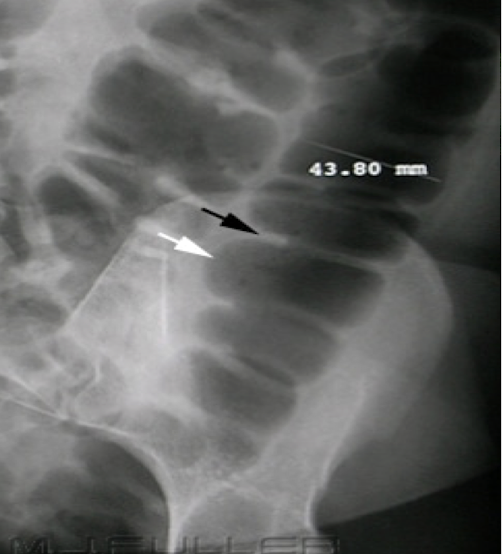

KUB (kidney, ureter & bladder)

XRAY optimized to assess the urogenital system ± GI system

Abdominal Radiograph

IVP (IV pyelogram)

XRAY using IV contrast material to assess kidney, ureters and bladder (less commonly used)

*CT Urogram is more common for assessing flank pain

Abdominal Radiograph

CT urography

CT scan using an IV contrast material to assess kidney, ureters, and bladder

Abdominal Radiograph